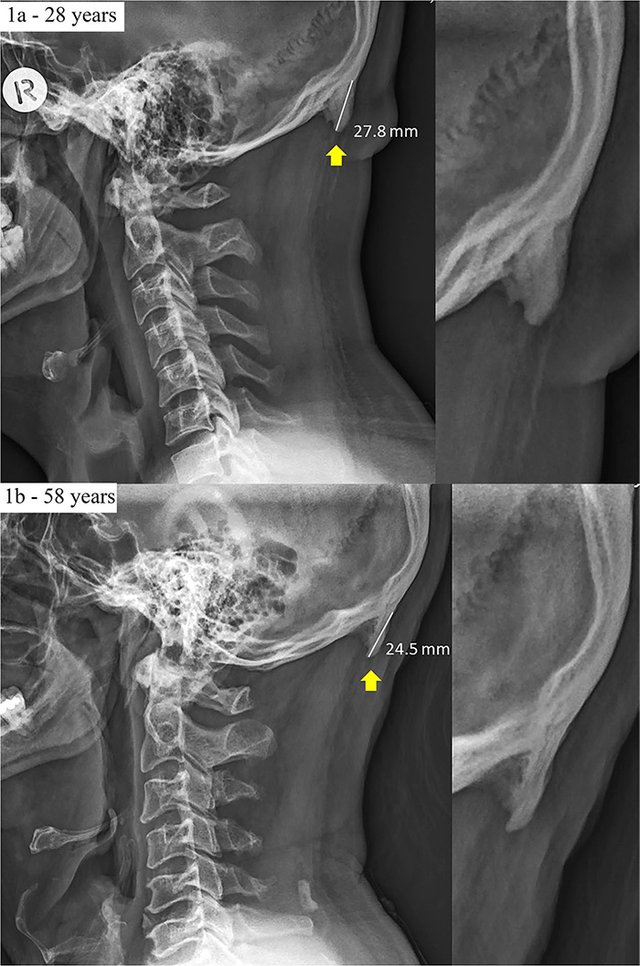

І ось тепер вчені з Квінслендського університету під час вивчення 218 рентгенівських знімків людей у віці від 18 до 30 років виявили, що у багатьох з них через смартфони розвиваються горби.

41% знімків дозволяв припустити про початок патологічного розростання в основі черепа, де відбувається його з'єднання з шиєю. Коли шия постійно нахилена, то вага голови, яка становить, у середньому, 4-5 кг, переноситься з кісток хребта на м'язи задньої частини голови та шиї. Через хронічне перевантаження може почати утворюватися горб, як вважають вчені. Йдеться про розростання, яке у медицині називається зовнішнім потиличним виступом. Зазвичай його виявляють у людей похилого віку в результаті десятиліть надмірного тиску на скелет.

Однак сучасна мода на гаджети привела до того, що це утворення почало виникати значно раніше. Сьогодні скелетно-м'язовий дегенеративний процес може стартувати з раннього віку, підкреслюють автори дослідження. Щоби мінімізувати шкоду, потрібно просто менше користуватися смартфонами та іншими пристроями.